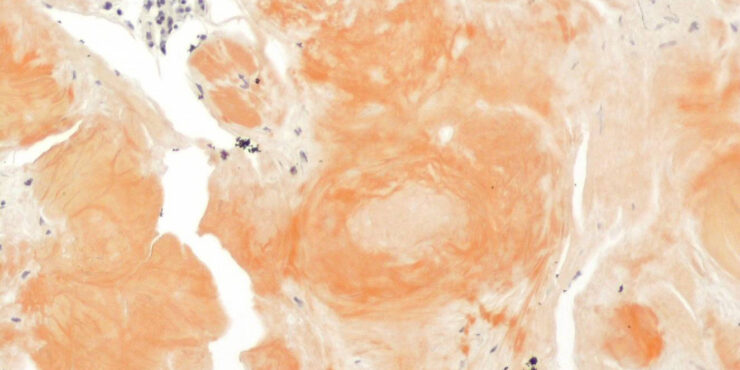

Read MoreNoninflammatory thrombi = الصمامة غير الالتهابية